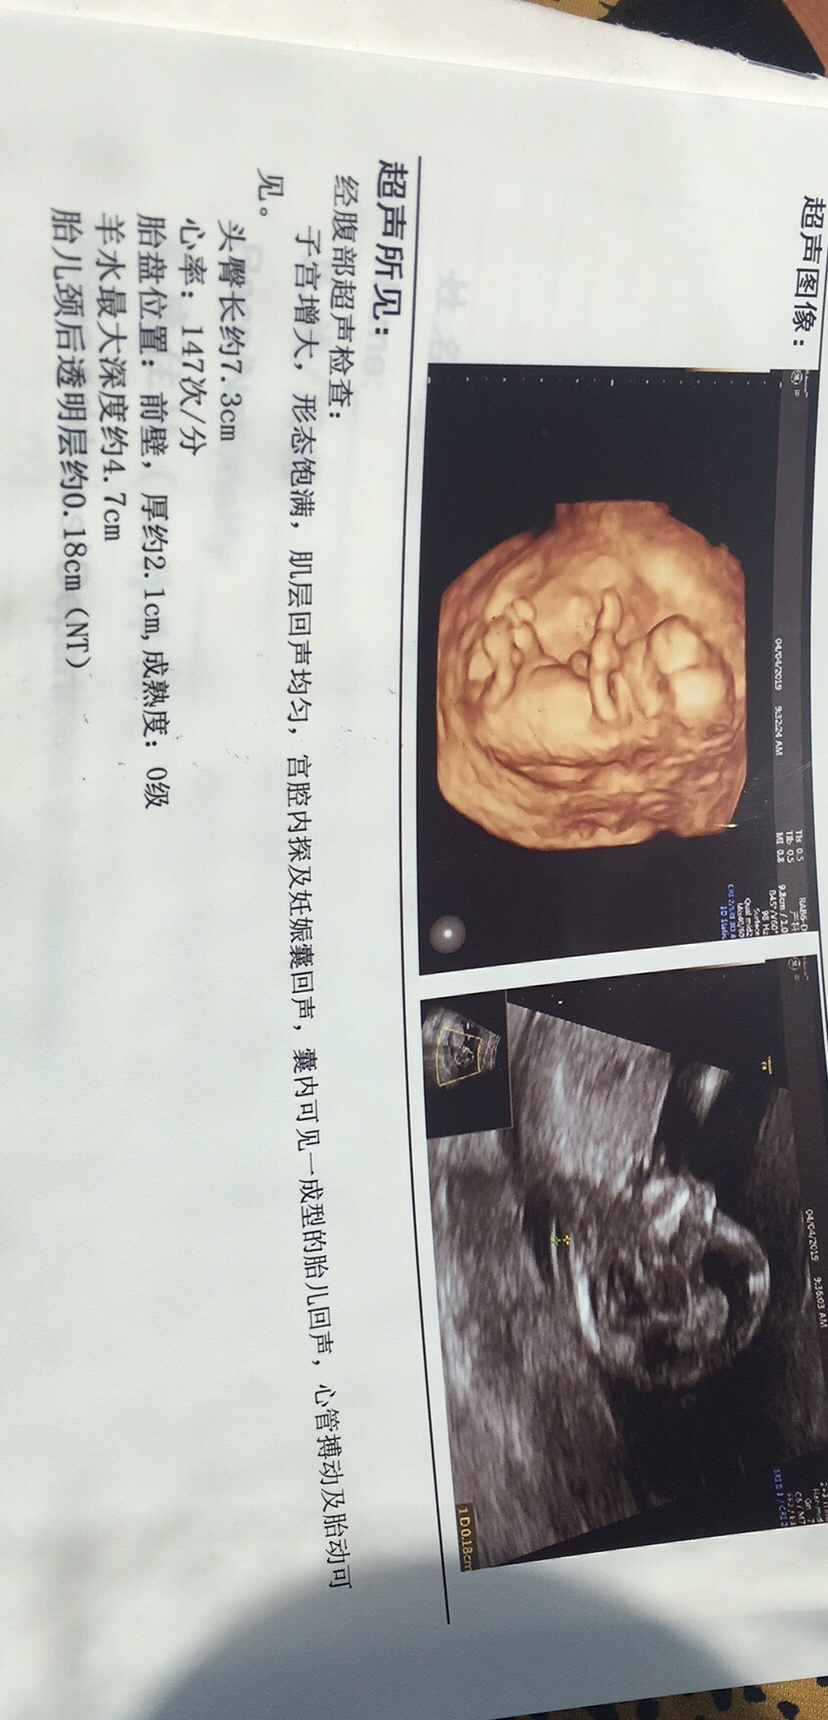

孕9周+3天